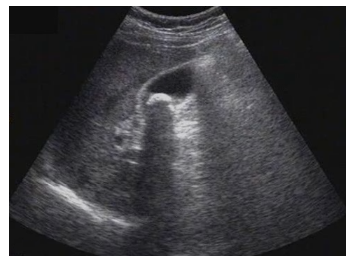

试题3:患者女性,50岁,间断上腹隐痛半年,诊断为(2分)

A.肝癌

B.肝硬化

C.胆囊结石

D.肾结石

E.急性胆囊炎

【答案】C